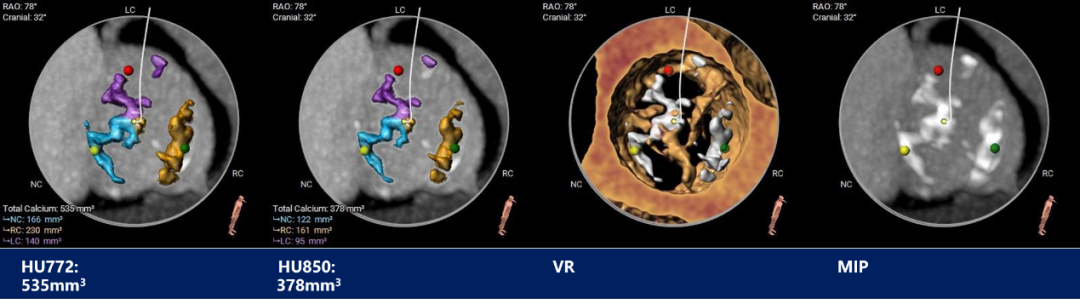

瓣上测量

瓣上测量:窦部发育均匀,瓣叶中重度钙化并明显增生肥厚,钙化分布相对均匀,主要分布在瓣叶边缘及管壁附着缘,左无窦间有部分钙化粘连。